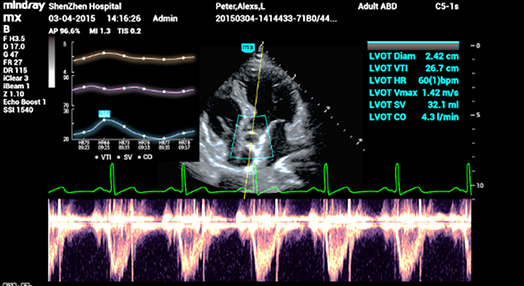

2Smart VTI

Automatische meting van de VTI (Velocity Time Integral ) en CO (Cardiac Output), voor een snelle beoordeling van de hartfunctie. Zoek automatisch het kleurvlak en de PW-samplelijn in realtime. Een grafiek met parametertrends over CO, SV en VTI om de besluitvorming te ondersteunen.